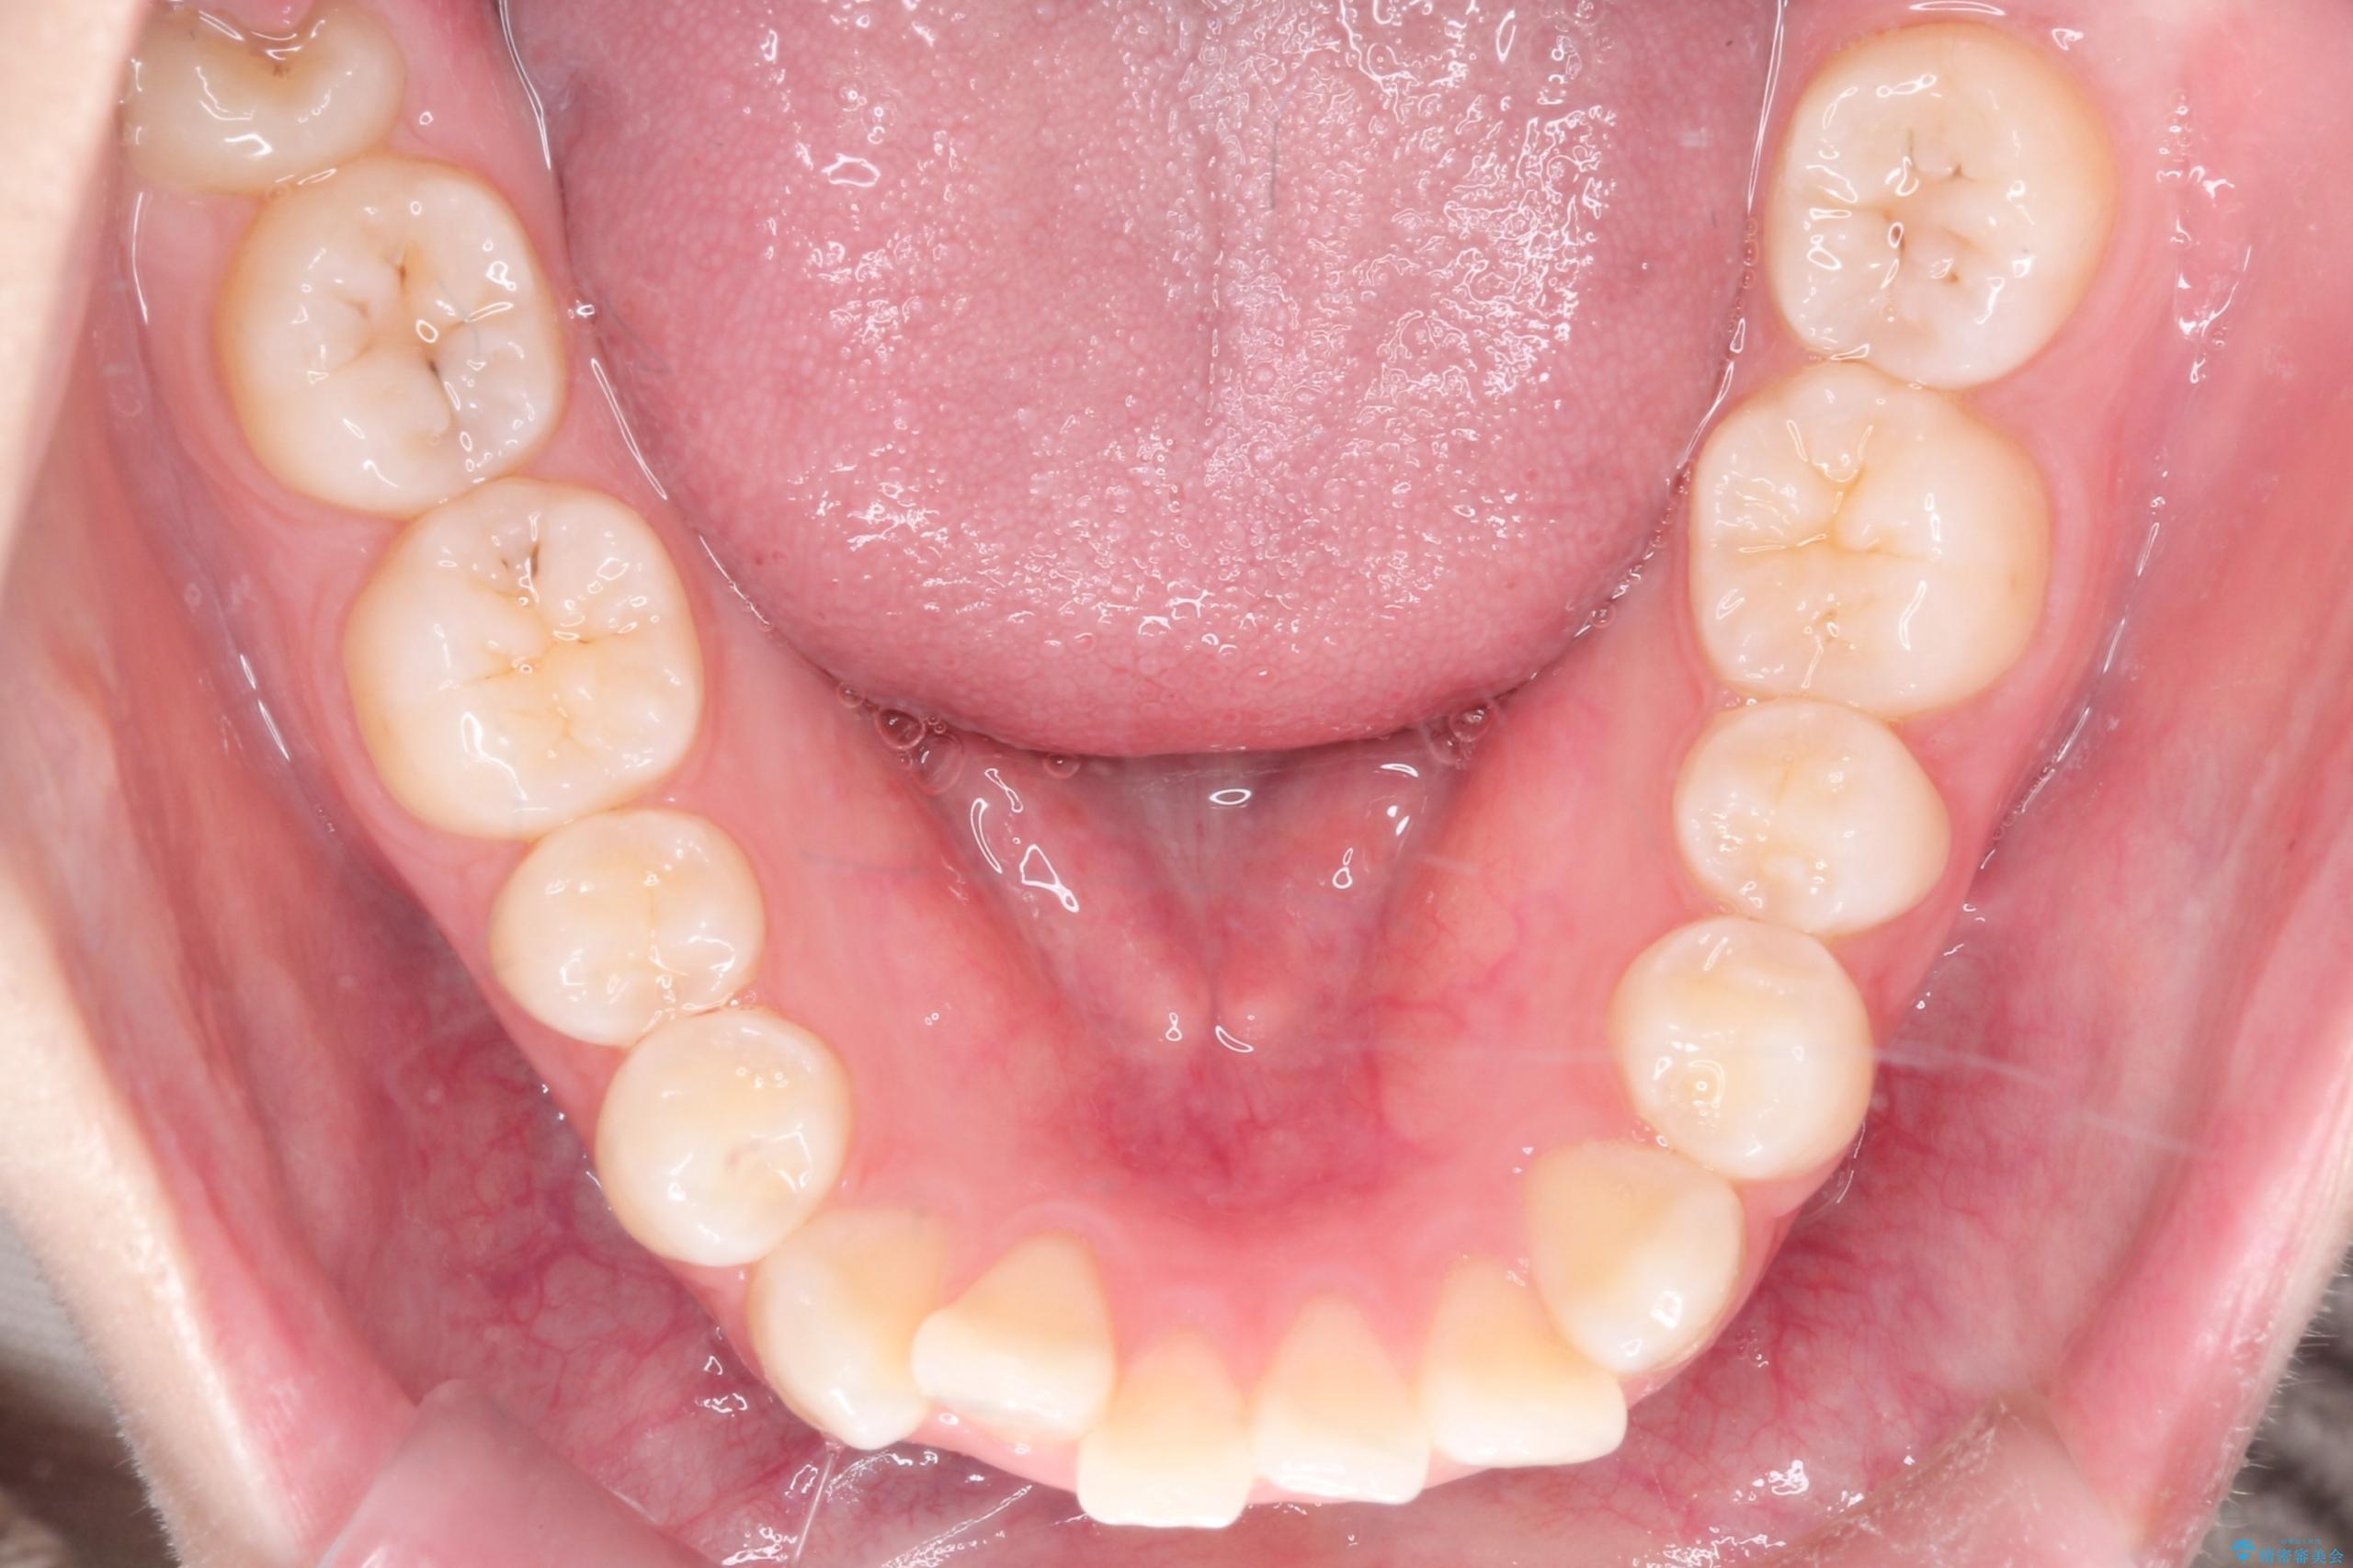

- 前歯のデコボコ(叢生)を気にされてご来院されました。精密な検査の結果、歯が並ぶスペースが不足していることが判明。患者様のご希望から、透明で目立ちにくいインビザライン(マウスピース矯正)による治療計画を立案しました。抜歯を避け、奥歯全体を奥へ動かす遠心移動という方法でスペースを確保し、前歯の叢生を解消することを目指します。

今回の矯正治療では、透明なマウスピース型の装置インビザラインを使用しました。この装置は取り外し可能で、日常生活で目立ちません。治療は、緻密に計算された計画に基づき、段階的に作製されたマウスピースを交換していくことで、奥歯から順に全体を後方へ移動させる遠心移動を実施。これにより、前歯を並べるための十分なスペースが確保され、デコボコが解消されました。抜歯することなく、機能的にも審美的にも整った美しい歯並びを獲得していただけました。